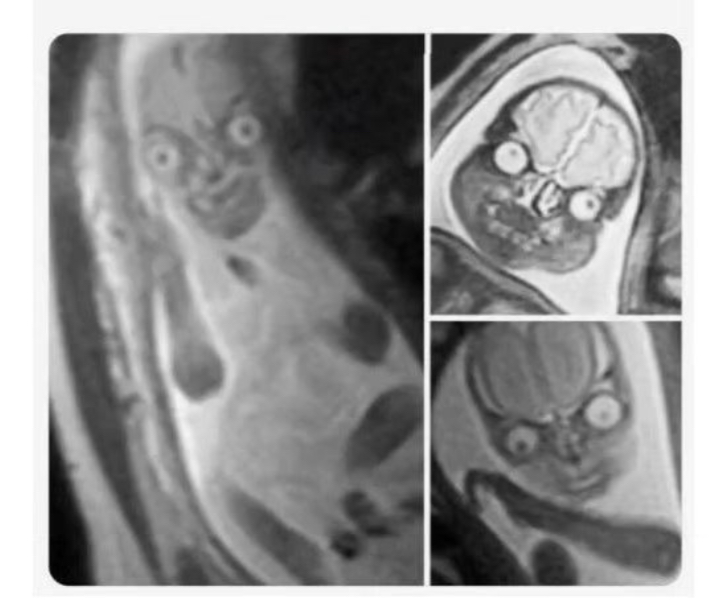

임산부가 초음파 하는 이유

​MRI로 태아를 찍으면

이렇게 나와서